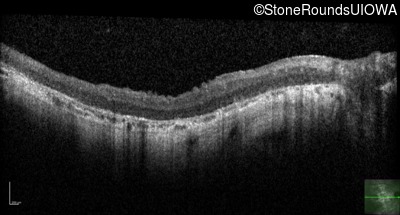

OD OS

Age at visit: 33 years